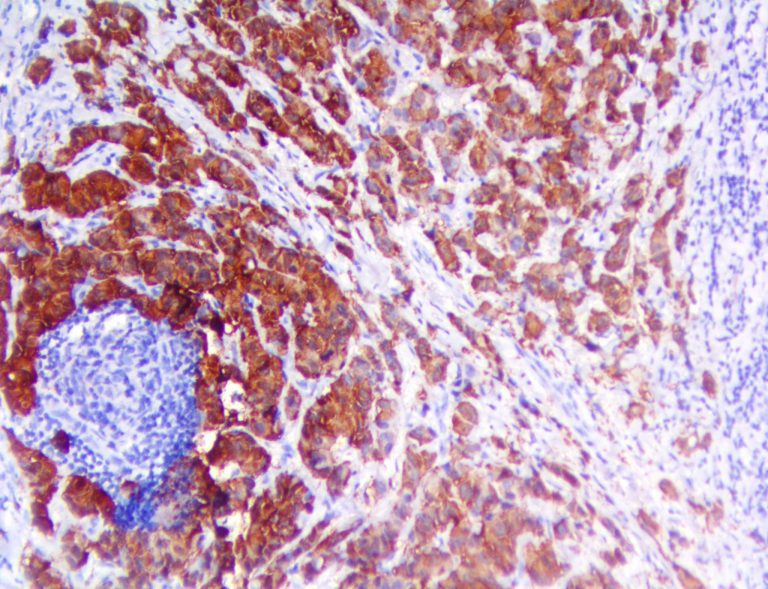

It is the ICU physician who is most likely to witness one of the deadliest manifestations of the abnormal immunological response, the cytokine storm syndrome (CSS). This response is also referred to by some as the cytokine release syndrome (CRS). CSS is characterized by continuous activation and expansion of macrophage and lymphocyte populations, which secrete large amounts of cytokines, causing the cytokine storm. This massive cytokine release is akin to hemophagocytic lymphohistiocytosis (HLH) disease, a syndrome characterized by initial unchecked and persistent activation of cytotoxic T lymphocytes and NK cells.

Clinical and laboratory manifestations of HLH include fever, enlarged liver and/or spleen, neurologic dysfunction, coagulopathy, liver dysfunction, cytopenias (i.e., low levels of erythrocytes, leukocytes, and/or platelets), hypertriglyceridemia, hyperferritinemia, hemophagocytosis, and eventually diminished NK cell activity as the immune system becomes progressively paralyzed. HLH can be familial (primary HLH) or secondary to another disease process (sHLH), such as rheumatic disease, in which it is referred to as macrophage activation syndrome (MAS, characterized by elevated ferritin).